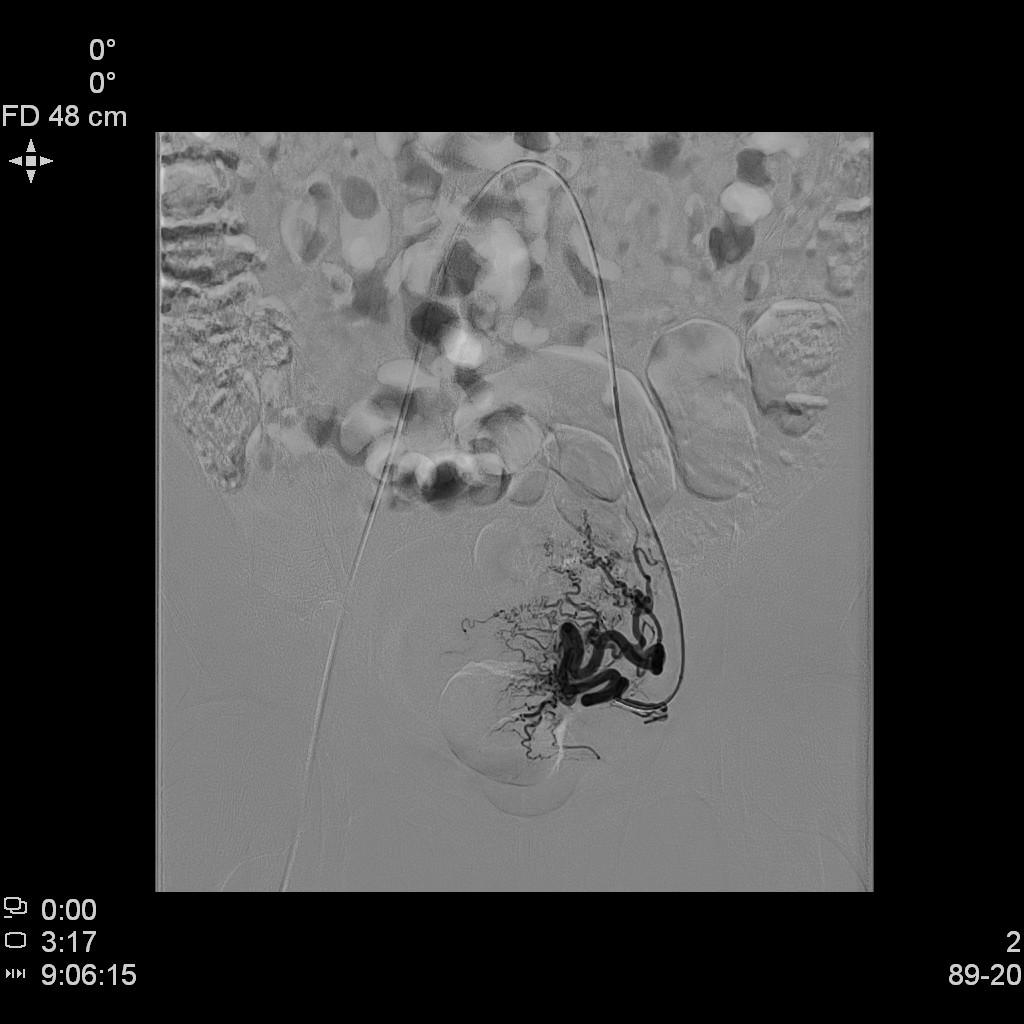

中年女性,发现子宫肌瘤进行性增大5年余。复查彩超提示多发肌瘤,较前明显增大(最大者直径近10cm)。近半年尿频、尿急症状进行性加重,考虑增大的子宫肌瘤压迫膀胱所致。

- MRI检查显示显示多发子巨大宫肌瘤,压迫膀胱。

MRI显示多发子巨大宫肌瘤,压迫膀胱

- 经桡动脉入路置入导管造影显示双侧子宫动脉明显增粗,染色丰富,子宫明显增大。

腹主动脉造影

- 进一步超选插管右侧髂内动脉造影确认子动脉开口位置。

右侧髂内动脉造影

- 微导管进一步超选插管右侧子宫动脉主干造影确认位置。

右侧子宫动脉造影